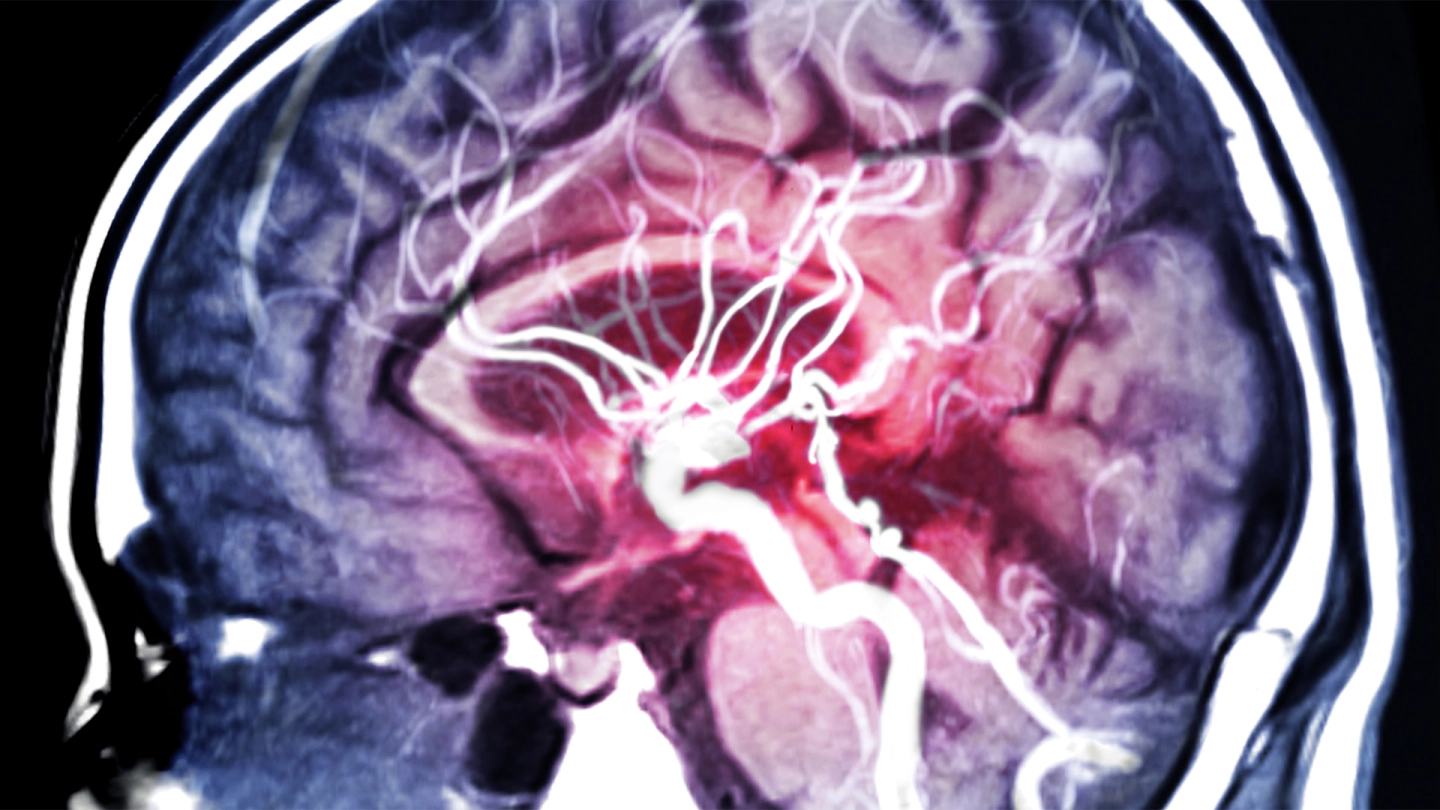

Ein Hirnaneurysma ist eine Ausbuchtung einer Schlagader im Gehirn. Viele Menschen, die ein Aneurysma haben, bemerken davon ihr Leben lang nichts. Manchmal wird es zufällig entdeckt. Bestimmte Faktoren erhöhen das Risiko, dass es reißt und eine lebensbedrohliche Hirnblutung auslöst.

Aneurysmen können an verschiedenen Arterien entstehen, beispielsweise an der Hauptschlagader im Bauch. Befindet sich die Wölbung an einer Schlagader des Gehirns, spricht man von einem Hirnaneurysma oder Hirnarterienaneurysma. Häufig bilden sich solche Aneurysmen an Verzweigungsstellen der Arterien, über die das Gehirn mit Blut versorgt wird. Wenn ein Hirnaneurysma reißt, kommt es zu einer lebensbedrohlichen Hirnblutung.

Bei häufigen Kopfschmerzen oder Sehstörungen kann man mit einer Magnetresonanztomographie (MRT) oder eine Computertomographie (CT) die Ursache für die Beschwerden ermitteln.

Mit einer digitalen Subtraktionsangiographie (DSA) lassen sich Aneurysmen besonders gut sichtbar machen: Dabei wird eine Röntgenaufnahme mit und eine Aufnahme ohne Kontrastmittel gemacht. Daraus kann der Computer anschließend ein Bild errechnen, auf dem nur noch die Blutgefäße zu sehen sind.